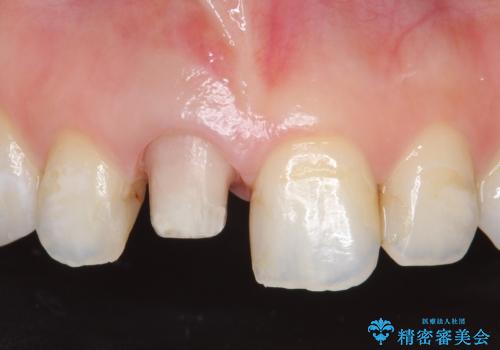

- 右上1番目の歯の変色が気になると来院された方の症例です。

検査の結果、右上1の歯は失活(歯の神経が死んでいること)していたため根管治療を行いました。

その後オールセラミッククラウン(スペシャル)による補綴を行いました。

なお隣在歯の樹脂は今後治療していく予定です。